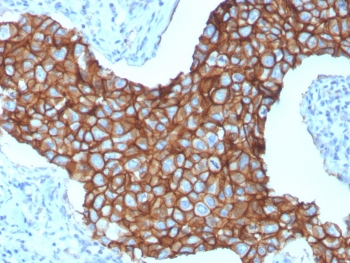

HER2 Antibody Breast Cancer IHC. Immunohistochemistry analysis of FFPE human breast carcinoma tissue using HER2 Antibody (clone ERBB2/3257) demonstrates strong HRP-DAB brown membranous staining outlining tumor epithelial cells, consistent with ErbB2 / HER2 overexpression as a receptor tyrosine kinase in breast cancer, while surrounding stromal tissue shows minimal signal; nuclei are counterstained blue. HIER: boil tissue sections in pH 6 10 mM citrate buffer for 10-20 min and allow to cool before testing.

HER2 Antibody Breast Tumor Membrane IHC. Immunohistochemistry analysis of FFPE human breast carcinoma tissue using HER2 Antibody (clone ERBB2/3257) highlights intense, continuous HRP-DAB brown membranous staining across tumor cell clusters, emphasizing cell surface localization of ErbB2 / HER2 as a receptor tyrosine kinase, while adjacent stromal regions remain largely negative; nuclei are counterstained blue. HIER: boil tissue sections in pH 6 10 mM citrate buffer for 10-20 min and allow to cool before testing.